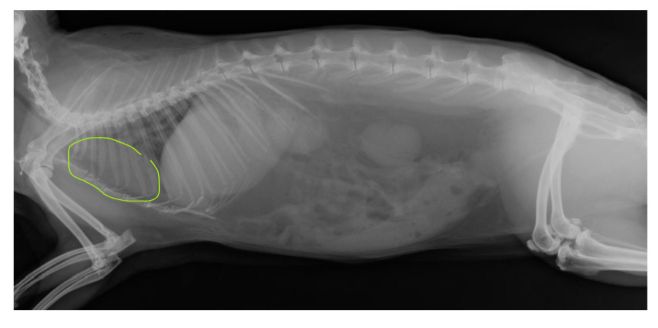

outline this radiograph:

what species

what do we notice about proportions?

what is a disadvantage to this body structure?

in which species do we see this layout?

rabbit

green = heart - rabbit has very small thorax proportional to abdomen, heart is very cranial

any thing can affect lungs and heart from the abdomen, e.g. reproduction as thoracic cavity is so small

hind gut fermenters